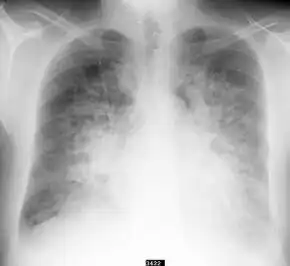

| Ultrasound of the lungs showing edema due to severe systolic heart failure[2] | |

Triggers may include not taking blood pressure medication, stimulant use, and stress.[1] Risk factors include hypertension, heart failure, and renal artery stenosis.[1] The underlying mechanism involves activation of the sympathetic nervous system which narrows blood vessels.[1][5] While fluid is present in the lung, fluid overload is typically not present.[1] Diagnosis is supported by low oxygen, mean arterial pressure > 120 mmHg, and ultrasound of the lungs.[1] It is a type of acute decompensated heart failure.[3]